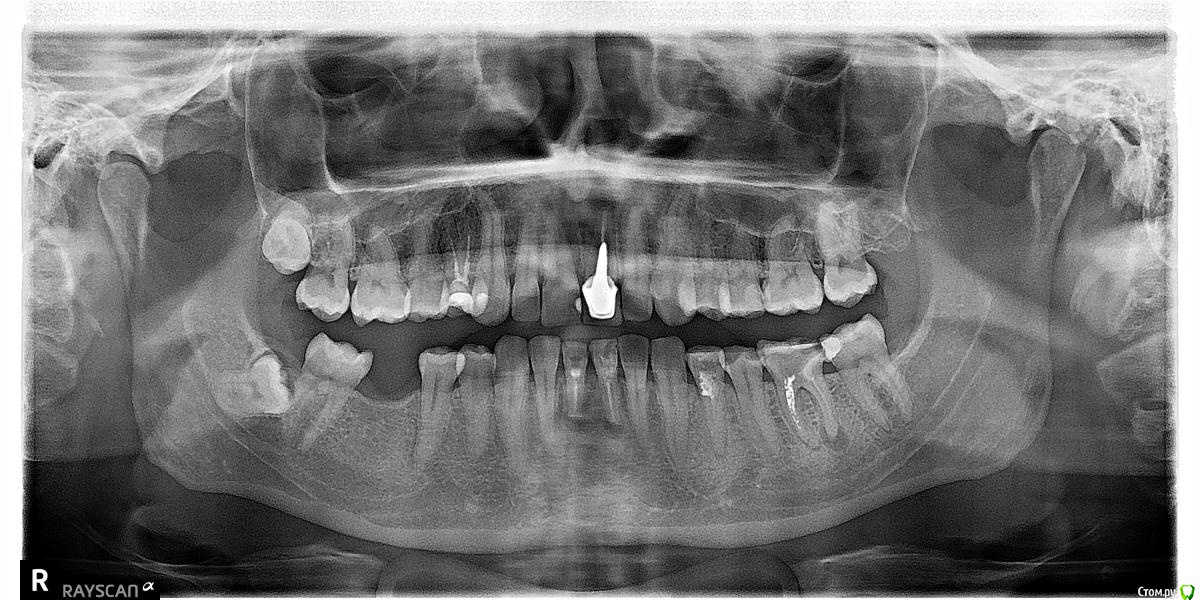

red_butler Опубликовано 7 ноября, 2018 Поделиться Опубликовано 7 ноября, 2018 О каком зубе речь? Если судить только по снимку, то несколько зубов требуют лечения каналов. Ссылка на комментарий

irakesha Опубликовано 7 ноября, 2018 Автор Поделиться Опубликовано 7 ноября, 2018 О каком зубе речь? Если судить только по снимку, то несколько зубов требуют лечения каналов.1-ой левый моляр? Снизу. Не совсем понимаю, как правильно его обозначить. Справа такой же у меня отсутствует. Ссылка на комментарий

red_butler Опубликовано 7 ноября, 2018 Поделиться Опубликовано 7 ноября, 2018 1-ой левый моляр? Снизу. Не совсем понимаю, как правильно его обозначить. Справа такой же у меня отсутствует. Если судить только по рентгену, то лечить и протезировать 1 Ссылка на комментарий

DmitrySH Опубликовано 7 ноября, 2018 Поделиться Опубликовано 7 ноября, 2018 Проблема в том, что я живу в Доминикане, к врачам обращаюсь впервые и по страховке. Подобные зубы по страховке обычно лечат, просто удаляют.. Если судить только по снимку, то лечение вполне возможно. Ссылка на комментарий